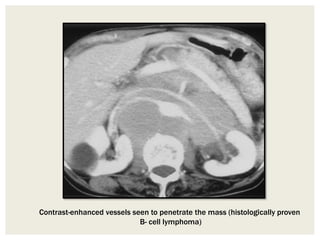

Lesions That Extend Between Normal Structures

Some tumors grow and extend into spaces between preexisting

structures and surround vessels without compressing their lumina.

Lymphangiomas and ganglioneuromas are examples of such

tumors.

Another entity with this growth pattern is lymphoma. This

neoplasm tends to surround adjacent vessels, manifesting with the

“CT angiogram sign” or “floating aorta sign”

Contrast-enhanced vessels seen to penetrate the mass (histologically proven

B- cell lymphoma)